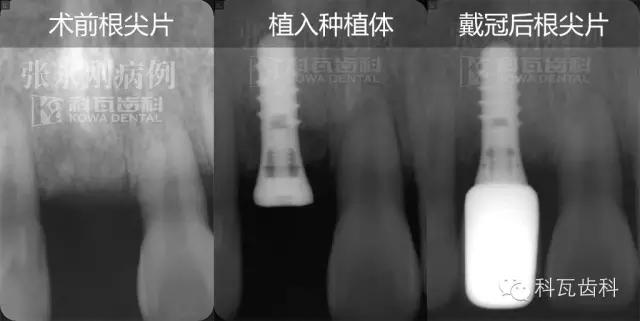

術(shù)前牙根片顯示:雖然缺牙時間較長,但是缺牙部位牙槽骨高度密度均可

2013年3月2日,采用微創(chuàng)種植牙技術(shù),為缺牙部位植入一顆ITI4.1/10RNSP種植體,手術(shù)順利,術(shù)后佩戴臨時牙冠,不影響正常的咀嚼以及美觀度。

5、2個月后,佩戴全瓷冠

佩戴全瓷冠后,修復(fù)后的牙齒和自然牙渾然一體,幾乎無法辨別,自然、美觀、和諧。客人滿意。